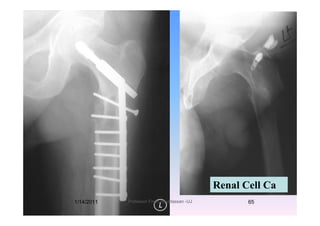

Renal Cell Ca

1/14/2011 65Professor Freih AbuHassan -UJ

Needs ProximalNeeds Proximal

Femoral Replacement

Subtrochanteric fractureSubtrochanteric fracture

Reconstruction nail with locking

l th f l kscrews along the femoral neck.

reduces the risk of subsequent NOF fracturereduces the risk of subsequent NOF fracture

if th f t f il t it i tiif the fracture fails to unite, persisting

pain may result in revision surgery orpain may result in revision surgery or

even Proximal Femoral Replacement.p

1/14/2011 64Professor Freih AbuHassan -UJ